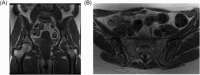

Gaucher disease (GD) is a rare, genetic lysosomal disorder leading to lipid accumulation and dysfunction in multiple organs. Involvement of the skeleton is one of the most prevalent aspects of GD and a major cause of pain, disability, and reduced quality of life. Uniform recommendations for contemporary evaluation and management are needed. To develop practical clinical recommendations, an international group of experienced physicians conducted a comprehensive review of 20 years' of the literature, defining terms according to pathophysiological understanding and pointing out best practice and unmet needs related to the skeletal features of this disorder. Abnormalities of bone modeling, reduced bone density, bone infarction, and plasma cell dyscrasias accompany the displacement of healthy adipocytes in adult marrow. Exposure to excess bioactive glycosphingolipids appears to affect hematopoiesis and the balance of osteoblast and osteoclast numbers and activity. Imbalance between bone formation and breakdown induces disordered trabecular and cortical bone modeling, cortical bone thinning, fragility fractures, and osteolytic lesions. Regular assessment of bone mineral density, marrow infiltration, the axial skeleton and searching for potential malignancy are recommended. MRI is valuable for monitoring skeletal involvement: It provides semiquantitative assessment of marrow infiltration and the degree of bone infarction. When MRI is not available, monitoring of painful acute bone crises and osteonecrosis by plain X-ray has limited value. In adult patients, we recommend DXA of the lumbar spine and left and right hips, with careful protocols designed to exclude focal disease; serial follow-up should be done using the same standardized instrument. Skeletal health may be improved by common measures, including adequate calcium and vitamin D and management of pain and orthopedic complications. Prompt initiation of specific therapy for GD is crucial to optimizing outcomes and preventing irreversible skeletal complications. Investing in safe, clinically useful, and better predictive methods for determining bone integrity and fracture risk remains a need. © 2019 The Authors. Journal of Bone and Mineral Research Published by Wiley Periodicals Inc.